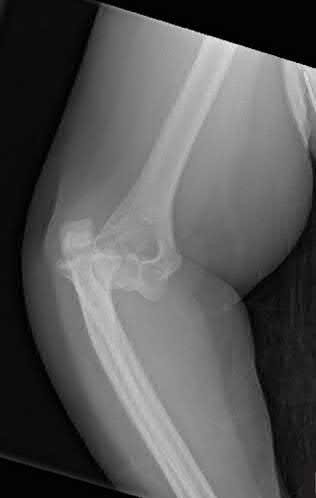

A 45-year-old man sustains a high-energy knee injury in a motorcycle accident.

Based on the Schatzker classification, a bicondylar tibial plateau fracture with complete dissociation of the metaphysis from the diaphysis is classified as:

Explanation

A Schatzker VI fracture is defined by complete metaphyseal-diaphyseal dissociation, often accompanied by severe soft tissue injury. Schatzker V is a bicondylar fracture but maintains continuity between the articular segment and the diaphysis. Schatzker I-III involve the lateral plateau, and IV involves the medial plateau.